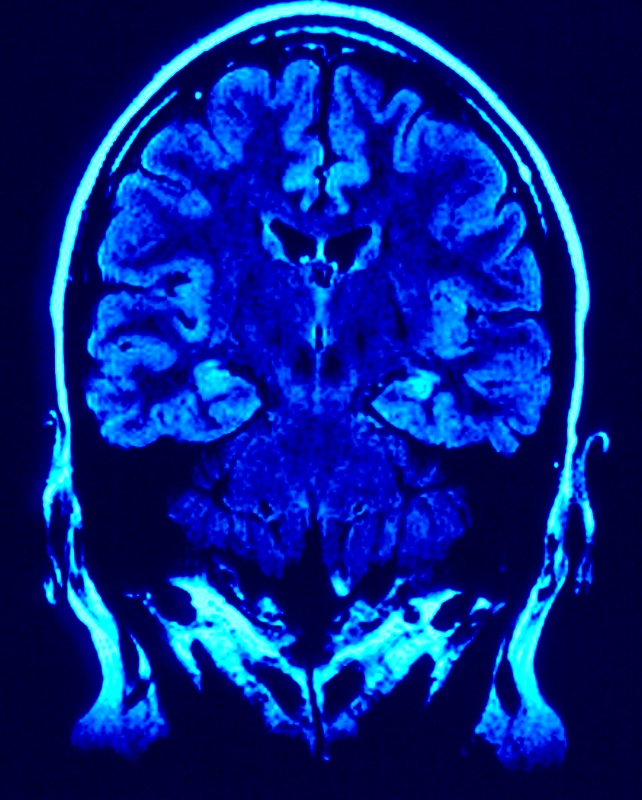

The relationship between the brain and the body cannot be denied. There are techniques, such as Neuro Emotional Technique (N.E.T.) and Emotional Freedom Tapping (E.F.T),  that help with the mind-body connection in physical health.